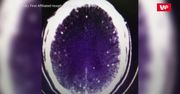

To historia o tym, jak ważne jest, by zanim zjemy mięso, odpowiednio je przygotować. Pewien 46-letni pracownik budowy w Chinach kupił wieprzowinę i baraninę, by przygotować danie w ognistym kociołku. Kilka dni po uczcie zaczęło mu się kręcić w głowie, odczuwał ból, a w nocy dostawał napadów podobnych do padaczki. Podejrzane objawy zauważyli współpracownicy mężczyzny, którzy natychmiast odwieźli go do szpitala. Lekarze wykryli zwapnienia w czaszce, ale pacjent odmówił dalszych badań ze względów finansowych. 46-latek zgłosił się jednak drugi raz do szpitala, gdy okazało się, że napady silnych drgawek nie ustępują. Dzięki rezonansowi magnetycznemu zdiagnozowano w jego mózgu wągrzycę. To choroba pasożytnicza wywołana przez postacie larwalne tasiemca. Wywołało ją zanieczyszczone wągrami i jednocześnie niedogotowane mięso wieprzowe ze wspomnianego kociołka. 46-latek wyzdrowiał, gdy lekarze usunęli tasiemce z jego mózgu. Choć przypadek z Chin jest dość ekstremalny, to wągrzycą można zarazić się wszędzie. Wystarczy, że kupimy nieprzebadane lub zanieczyszczone mięso z podejrzanego źródła i dodatkowo go nie dogotujemy.